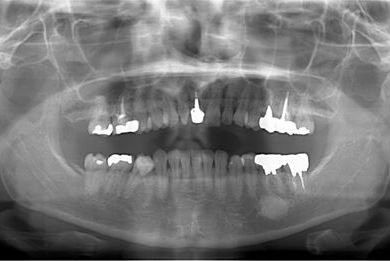

| 性別/年齢 | 女性 / 38歳 | ||||||||||||||||||||||||||||||||

| 主訴 | 右奥歯2本、インレーの相談をしたい。 | ||||||||||||||||||||||||||||||||

| 治療方針 | セラミック治療にて、審美的回復を行う。 | ||||||||||||||||||||||||||||||||

| 治療内容 | ハイブリッドセラミックインレー2本、メタルボンドセラミッククラウン2本(メタルボンド用土台2本)、オールセラミッククラウン1本(オールセラミック用土台1本) | ||||||||||||||||||||||||||||||||

| 総治療費 | 495,758円 | ||||||||||||||||||||||||||||||||

| 治療期間 | 1年6ヶ月 |